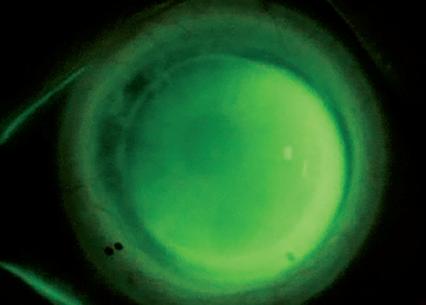

Een 53-jarige man wordt doorverwezen voor een sclerale contactlensaanpassing na een corneatransplantatie van het linkeroog wegens keratoconus. De hulpvraag bestaat uit het verbeteren van het zicht van het linkeroog. De ongecorrigeerde visus OS bedraagt 0,05. Met een brilcorrectie van +1,25 –7,00 x 25 wordt een visus van 0,50 bereikt. Er wordt een diagnostische passing uitgevoerd met een Zenlens® scleralens (Bausch + Lomb) met de volgende parameters: basiskromming (BC) 7.42 mm, diameter 15.4 mm, sagittale hoogte (SAG) 4600 µm en APS flat 2 x steep 2. De overrefractie bedraagt plano –4,00 x 25. Bij beoordeling van de passing werd een superior-nasale randlift gezien, passend bij een licht te vlakke passing. Daarnaast was er sprake van een inferiortemporale decentratie. De hoge cilinderwaarde bij overrefractie wees op toriciteit-geïnduceerde lensflexie. Het fluoresceïnepatroon toonde duidelijke variatie in clearance, passend bij een sterk torisch hoornvlies (Afbeelding 1A). Bij sterk torische corneae kan een onvoldoende vault in bepaalde meridianen leiden tot schijnbare corneale aanraking. Een klassieke benadering is het kiezen voor een grotere diameter en/of grotere sagittale hoogte

BESPREKING

Door toriciteit toe te voegen aan het lenssegment tussen de optische zone en de landingzone kan de lens beter worden uitgelijnd met de cornea, terwijl een sferische basiskromming en eventueel sferische sterkte behouden blijven. Deze passingstechniek staat bekend als Bi-Elevation: gebruik van twee verschillende sagittale hoogtes, overeenkomstig met de twee hoofdmeridianen van de cornea. Bij het beoordelen van de passing dient men de centrale clearance in beide hoofdmeridianen te evalueren: bij voldoende centrale clearance kan de SAG van één meridiaan afzonderlijk worden aangepast, bij onvoldoende clearance dient de SAG in één of beide meridianen te worden verhoogd of verlaagd en tegelijkertijd is de basiskromming aan te passen om de corneale uitlijning te optimaliseren, parallel aan de SAG-aanpassingen. In deze casus werd na setting een centrale clearance van 211 µm gemeten. De bestaande SAG-waarde van 4600 µm bleek voldoende voor de vlakste meridiaan. Om extra clearance te creëren ter hoogte van 4–5 uur en 10–11 uur, werd de globale basiskromming afgevlakt van 7.42 mm naar 8.04 mm, overeenkomend met ongeveer 3,5 dpt. Om de passing in de steilere meridiaan te optimaliseren en de landing beter te laten aansluiten, werd 200 µm extra sagittale hoogte toegevoegd. Dit resulteerde in een lens met Bi-Elevation SAGwaarden van 4600 x 4800 µm. Deze aanpassing maakt de SmartCurve®-zone en de limbal clearance zones steiler in de diepere meridiaan; dit leidt tot een meer regelmatigere midperifere clearance en een stabielere gelijkmatige landing over de volledige omtrek van de lens. De definitieve lens werd ontworpen met de volgende parameters: BC 8.04 mm, SAG 4600 x 4800 µm, diameter 15.4 mm en APS standaard. De passing van de nieuwe lens toonde een passend fluoresceïnepatroon met goede uitlijning en behield dezelfde rotatiepositie als de eerdere torische APS-lens (Afbeelding 1B).

Uitgesproken corneale toriciteit kan het aanpassen van sclerale lenzen bemoeilijken en aanleiding geven tot decentratie, conjunctivale prolaps en zones met zowel overmatige als onvoldoende clearance. Door gebruik te maken van een Bi-Elevation ontwerp kan de corneale toriciteit worden gecompenseerd op het niveau van de sagittale vault. Dit resulteert in een beter uitgelijnde en stabielere sclerale lenspassing.